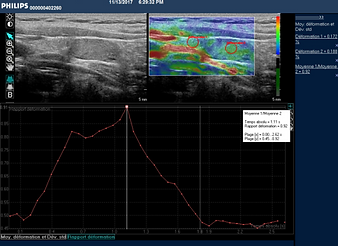

elastografía patológica

elastografía normal

Dos tipos de elastografía cuantitativa y semicuantitativa.